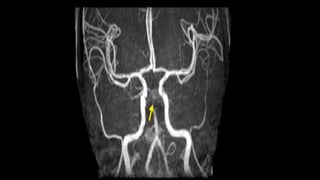

2D TOF MIP MRA 3D TOF VRT MRA

BILATERAL CAROTID MRA TOF MIP

LEFT ICA STENOSIS

• #63 Here is TOF MIP and VRT MRA showing excellent angiogram due to background suppression and better flow related signal leading to better distal small vessel visibilty

• #64 here is an example of AP VIEW of normal MR angiogram of cervicocranial arterial system

• #65 In this MR angiography of bilateral carotid system there is e/o short segment narrowing of Left ICA s/o left ICA stenosis